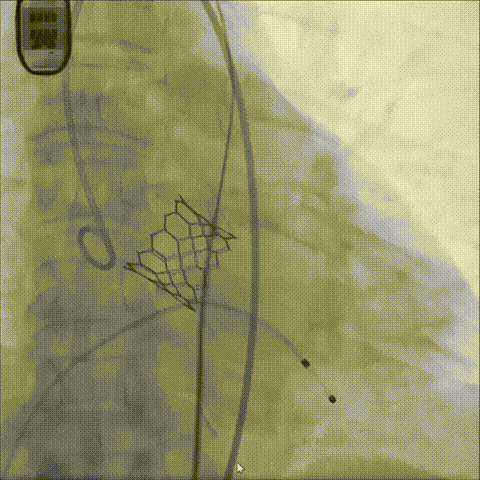

瓣膜释放